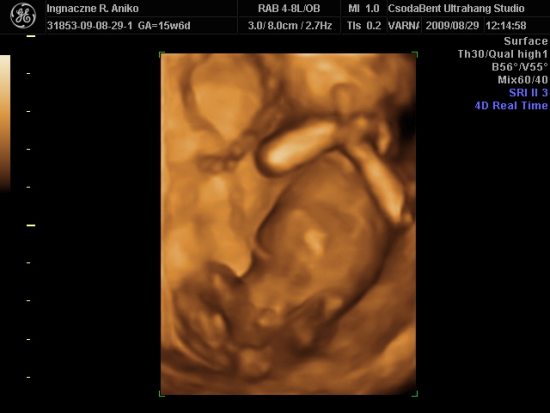

Lois is jelen